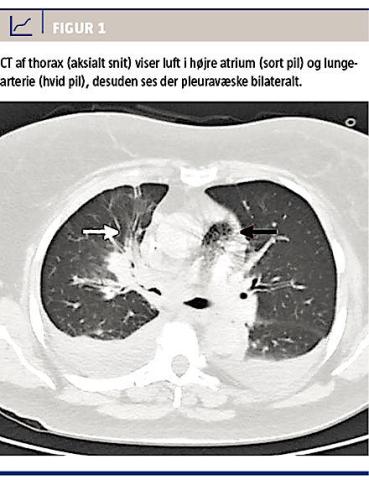

En 55-årig kvinde med dissemineret ovariecancer blev indlagt febril og dyspnøisk. Hun fik foretaget CeCT af thorax og abdomen, for at man kunne vurdere, om det var tiltagende vækst af metastaser, der var årsag til hendes symptomer. 100 ml kontrastvæske (iomeprol 350 mg/ml) blev injiceret med en motorsprøjte gennem højre vena cubiti. Umiddelbart efter kontrastindgiften blev patienten urolig, klagede over dyspnø og blev snart ukontaktbar, respirations- og pulsløs. På mistanke om anafylaksi udløst af kontrastvæsken blev der givet 0,3 mg adrenalin intramuskulært, hvorefter patienten genvandt bevidstheden. Hun var konfus, havde lav iltmætning (85-93%) og hyperventilerede. Hun fik 100% ilt på ventilationsmaske, hvorefter de vitale værdier normaliseredes. På fortsat mistanke om en allergisk reaktion blev der givet 2 mg clemastin i.v. Ved akut gennemgang af skanningsbillederne sås der luft i højre overarmsvener, hjertet, a. pulmonalis og ud i de små lungearterier bilateralt (Figur 1). Patienten blev lagt i Trendelenburgs leje med let venstredrejning (Durants manøvre), men dette udløste stort ubehag, og hun blev igen lejret på ryggen. Hun var fortsat stabil, men mere dyspnøisk end før skanningen og blev derfor